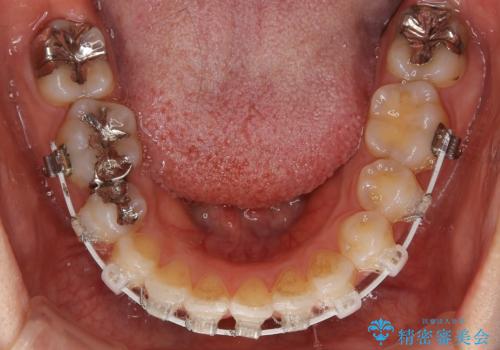

前歯のガタつきを改善 抜歯矯正後の後戻り

- 矯正装置

- 審美装置

- 抜歯矯正後の後戻りで前歯ガタつきが主訴で来院された患者様です。

後戻り矯正や非抜歯矯正はインビザラインをご案内する事が多いですが、自己管理の煩わしさから、目立たないワイヤー装置にて矯正治療を行うこととしました。

後戻りの程度としては軽度なので、治療期間としては短く終えることが出来ました。

前歯の正中線も改善され大変満足して頂きました。